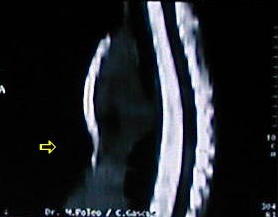

Reconstrucción Osea Tomográfica

• El esternón frente y lateral:

• observe la convexidad del cuerpo esternal y la concavidad que ocasiona el desplazamiento anterior del pronunciado apéndice sifoides.

• Las estructuras mediastinales se alojan en un tórax que ha disminuido su diámetro antero-posterior por la depresión esternal y la marcada concavidad de la columna dorsal.

• La reconstrucción ósea torácica tomográfica demuestra que las alteraciones presentes en el tórax están limitadas básicamente al defecto esternal.

• Los arcos cartilaginosos costales, causantes de los defectos del tórax están ausentes, en el proceso de reconstrucción tomográfica.